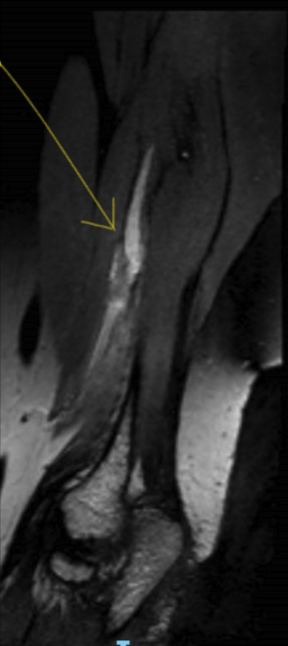

A 38-year-old female patient was assessed after a sudden onset of high radial nerve palsy without a history of preceding trauma. During the preceding 6 months, there was sensory disturbance and pain in the superficial radial nerve territory. Electrodiagnostic testing showed polyphasia in the brachioradialis and triceps and no other abnormalities. Imaging before referral with ultrasound and MRI showed a neuroma in the radial nerve in the vicinity of the lateral intermuscular septum (LIS) of the upper arm (Figure 1). Sudden deterioration in motor function and complete loss of sensory function in the radial nerve was accompanied by resolution of the neuropathic pain.

Following local review of the MRI, differential diagnosis included isolated inflammatory mononeuropathy, a granulomatous lesion of the radial nerve, perineurioma, or a malignant nerve sheath tumor. Repeat MRI neurography with diffuse tensor imaging was consistent with an atypical perineurioma with signal disruption and a complete lesion of the radial nerve at the level of the LIS with surrounding muscle edema.